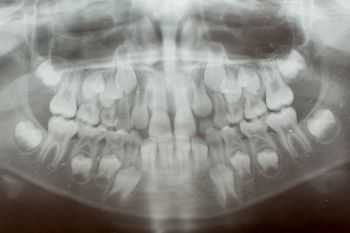

Материал и методы Нами была проанализирована 71 ортопантомограмма смешанного прикуса детей в возрасте от 6 до 13 лет, обследованных в 2001 - 2004 гг. по ортодонтическим показаниям. В зубной формуле каждого ребенка отмечали степень прорезывания коронки зуба (СПК) и степень формирования корня зуба (СФК). Напомним, что внечелюстной этап прорезывания коронки зуба имеет три степени: 1-я степень - появление над десной режущего края или бугра коронки; 2-я степень - прорезывание коронки до уровня экватора, 3-я степень - прорезывание всей коронки полностью [2].

В формировании корня зуба нами также были выделены три степени, соответствующие периодам его созревания: 1-я степень - рост корня в длину; 2-я степень - корень с несформированной верхушкой в виде раструба; 3-я степень - корень с незакрытой верхушкой.

Результаты и их обсуждение При сопоставлении СПК и СФК одного и того же зуба было выявлено, что 89 % зубов имеют одинаковое значение СПК и СФК. Из 11% зубов с различными значениями СПК и СФК у 78 % зубов СФК на одну единицу опережает СПК. Причем, у тех зубов, диапазон прорезывания которых меньше (у резцов и первых моляров), а, следовательно, и темпы их прорезывания выше, практически нет разницы между СПК и СФК [4].

Выводы Была выявлена сильная положительная корреляционная связь (коэффициент корреляции равен +0,99) между степенью прорезывания коронки зуба (выявляемого клинически во время осмотра зуба) и степенью формирования корня зуба (выявляемого рентгенологически). Следовательно, если коронка зуба имеет, к примеру, вторую степень прорезывания, то ее корень находится на 2-й или даже 3-ей степени своего формирования. Этот факт, несомненно, должен приниматься во внимание при планировании эндодонтического и ортодонтического лечения постоянных зубов, особенно при нежелательности или невозможности проведения рентгенологического исследования.